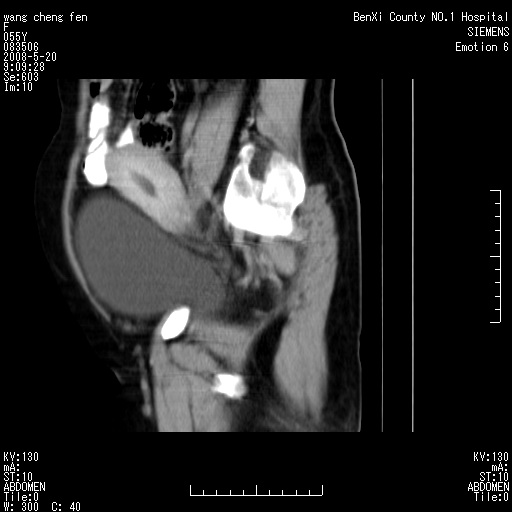

女、绝经后阴道流血3个月

左侧附件区可见一囊性占位,边缘清楚,内可见不规则形软组织影 ce:囊壁及内部可见强化 考虑 卵巢囊腺瘤

左侧附件区巨大囊实性病灶,边缘光整,病灶囊壁较厚,增强示囊壁及实性部分明显强化,强化呈度与宫体实质大致相同,宫腔积液征像,未见盆腔积液等其他异常,考虑左侧卵巢囊腺癌,不除外囊腺瘤及浆膜下肌瘤坏死

左侧附件区巨大囊实性病灶,边缘光整,病灶囊壁较厚,增强示囊壁及实性部分明显强化,强化呈度与宫体实质大致相同,宫腔积液征像,未见盆腔积液等其他异常。绝经后阴道流血3个月,结合病史左侧卵巢囊腺癌首先考虑,宫腔扩大不除外累及。期待结果。

支持浆膜下子宫肌瘤.之前由于网络原因未看全图片,现在重看,宫颈见一类圆形低密度影,增强轻度强化,低于肌层强化,宫腔扩大,考虑宫颈癌伴宫腔积液可能性大.

囊实性肿块分隔厚度较大,厚薄不均,增强实性成分明显强化,有不规则阴道流血,卵巢囊腺癌可能性大。

1,宫颈部占位,宫颈癌?2,左侧附件区囊实性占位,界较清,实质部分强化明显。考虑浆膜下或阔韧带肌瘤囊变可能大。囊腺类肿瘤不除外。